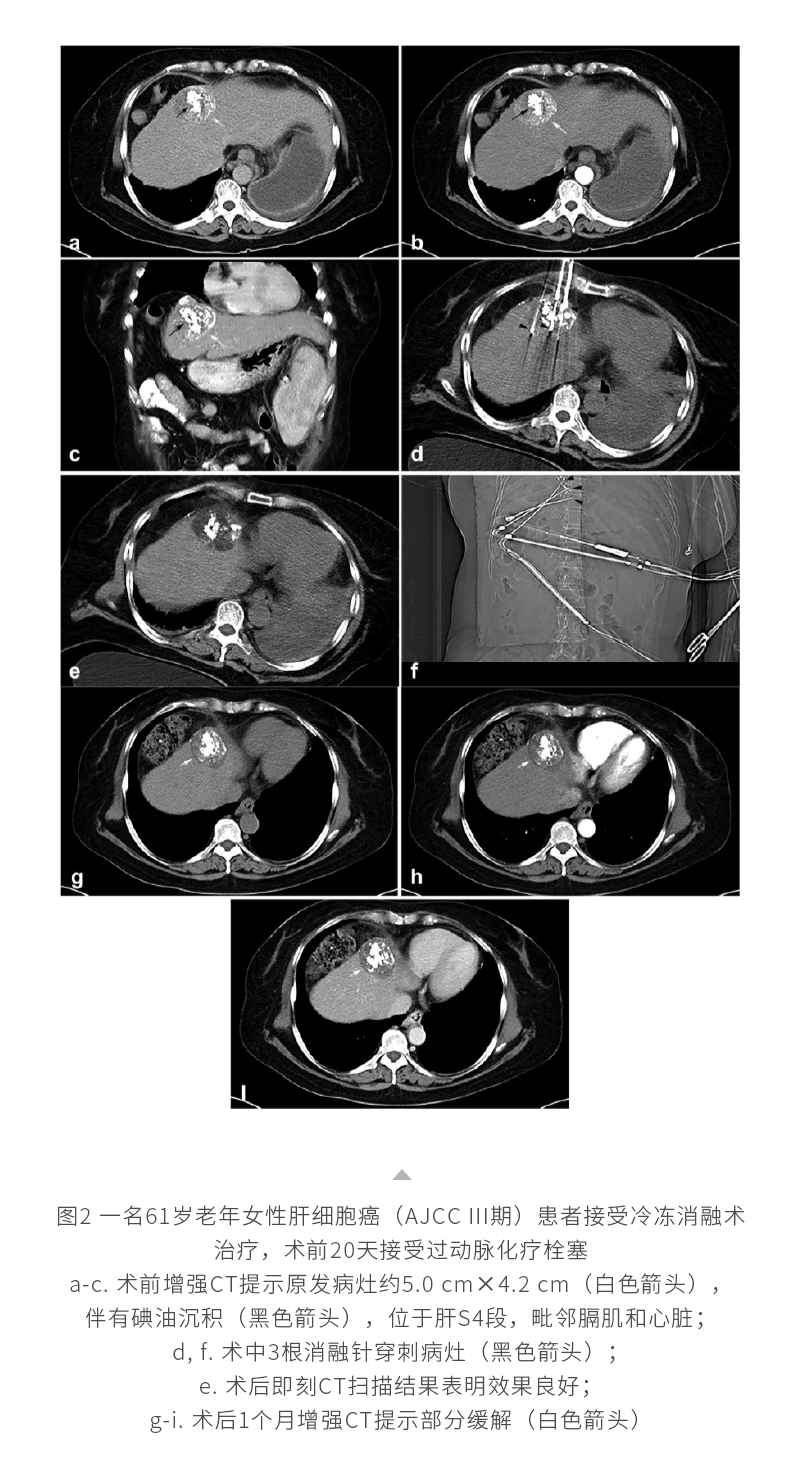

冷凍消融肝癌——【海杰亞科研資訊】第293期

發(fā)布時間:2024-12-06 | 作者:海杰亞 | 瀏覽次數(shù):972